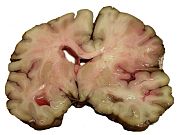

Intracranial hemorrhage is the accumulation of blood anywhere within the skull vault. A distinction is made between intra-axial hemorrhage (blood inside the brain) and extra-axial hemorrhage (blood inside the skull but outside the brain). Intra-axial hemorrhage is due to intraparenchymal hemorrhage or intraventricular hemorrhage (blood in the ventricular system). The main types of extra-axial hemorrhage are epidural hematoma (bleeding between the dura mater and the skull), subdural hematoma (in the subdural space) and subarachnoid hemorrhage (between the arachnoid mater and pia mater). Most of the hemorrhagic stroke syndromes have specific symptoms (e.g. headache, previous head injury).

Intracerebral hemorrhage (ICH) is bleeding directly into the brain tissue, forming a gradually enlarging hematoma (pooling of blood). It generally occurs in small arteries or arterioles and is commonly due to hypertension, trauma, bleeding disorders, amyloid angiopathy, illicit drug use (e.g. amphetamines or cocaine), and vascular malformations. The hematoma enlarges until pressure from surrounding tissue limits its growth, or until it decompresses by emptying into the ventricular system, CSF or the pial surface. A third of intracerebral bleed is into the brain's ventricles. ICH has a mortality rate of 44 percent after 30 days, higher than ischemic stroke or even the very deadly subarachnoid hemorrhage.